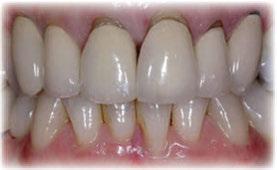

Figuras 18-21. Imágenes iniciales y finales de la paciente a los dos años de seguimiento donde observamos el cambio de la sonrisa y la recuperación de la dimensión vertical realizada con la rehabilitación sobre implantes y la confección de nuevas prótesis sobre implantes en el primer cuadrante y facetas en los sectores anteriores superiores e inferiores.